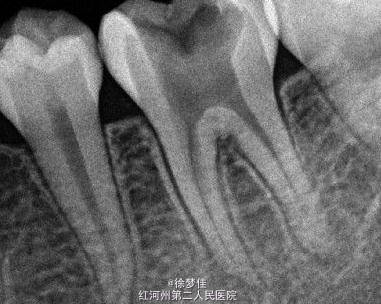

左下6近中根管断针X-P,断针长度约4MM, 根尖慢性炎症

插针确定断针根管,为近舌根管,插针有阻力,EDTA封存一周复诊。打开根管上部通路,根管大量清洗剂等冲洗,找到后,直接用超声根管搓15号带出断针。